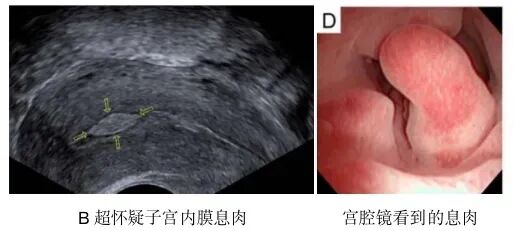

(2)子宫内膜息肉

子宫内膜息肉是另一种常见的子宫内膜异常状况。它本质上是子宫内膜组织的异常增生,常表现为乳头状的集聚形态。

子宫内膜息肉的临床表现差异较大,部分息肉可能无任何明显症状,仅在体检时偶然发现;也有部分患者会出现排卵前后异常出血、经期延长、月经量过多等问题。

在生育层面,息肉与粘连类似,可能会对胚胎着床造成阻碍。因此,一般建议对大小超过10mm的息肉进行切除处理。

需要注意的是,即使息肉体积较小,也不应轻易忽视。除了物理性的占位影响外,息肉还可能改变宫腔内的免疫环境。因此,对于不明原因反复妊娠失败的患者,建议重视息肉的干预。